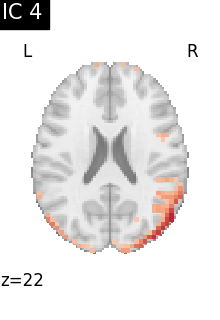

Finally, we plot the map for each ICA component separately

for i, cur_img in enumerate(iter_img(canica_components_img)):

plot_stat_map(

cur_img,

display_mode="z",

title=f"IC {int(i)}",

cut_coords=1,

vmax=0.05,

vmin=-0.05,

colorbar=False,

)

show()